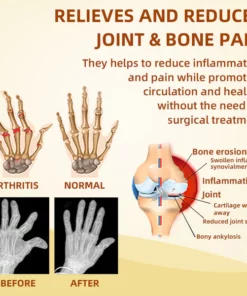

Cvreoz™ Cream effectively treats a wide range of joint problems. including osteoarthritis. rheumatoid arthritis. bursitis. tendonitis. osteoporosis. gout. carpal tunnel syndrome. ligament strains and sprains. thumb deformities. and tennis elbow. among other.

- Relieve Arthritis Pain

- Eliminate joint inflammation

- Eliminates cysts and edema

- Promotes joint tissue repair

- Improve joint elasticity and mobility

- Promotes joint repair and regeneration